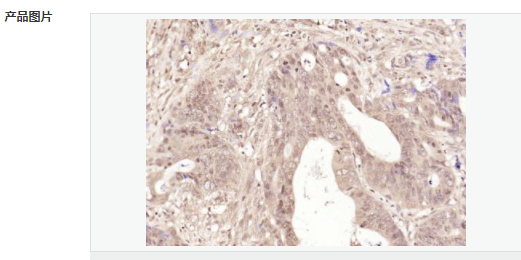

交叉反應(yīng):Human(predicted:Pig) 推薦應(yīng)用:IHC-P,IHC-F,ICC,IF,Flow-Cyt,ELISA

交叉反應(yīng):Human(predicted:Pig) 推薦應(yīng)用:IHC-P,IHC-F,ICC,IF,Flow-Cyt,ELISA

| 產(chǎn)品應(yīng)用 | ELISA=1:5000-10000 IHC-P=1:100-500 IHC-F=1:100-500 Flow-Cyt=1μg/Test ICC=1:100-500 IF=1:100-500 (石蠟切片需做抗原修復(fù)) not yet tested in other applications. optimal dilutions/concentrations should be determined by the end user. |